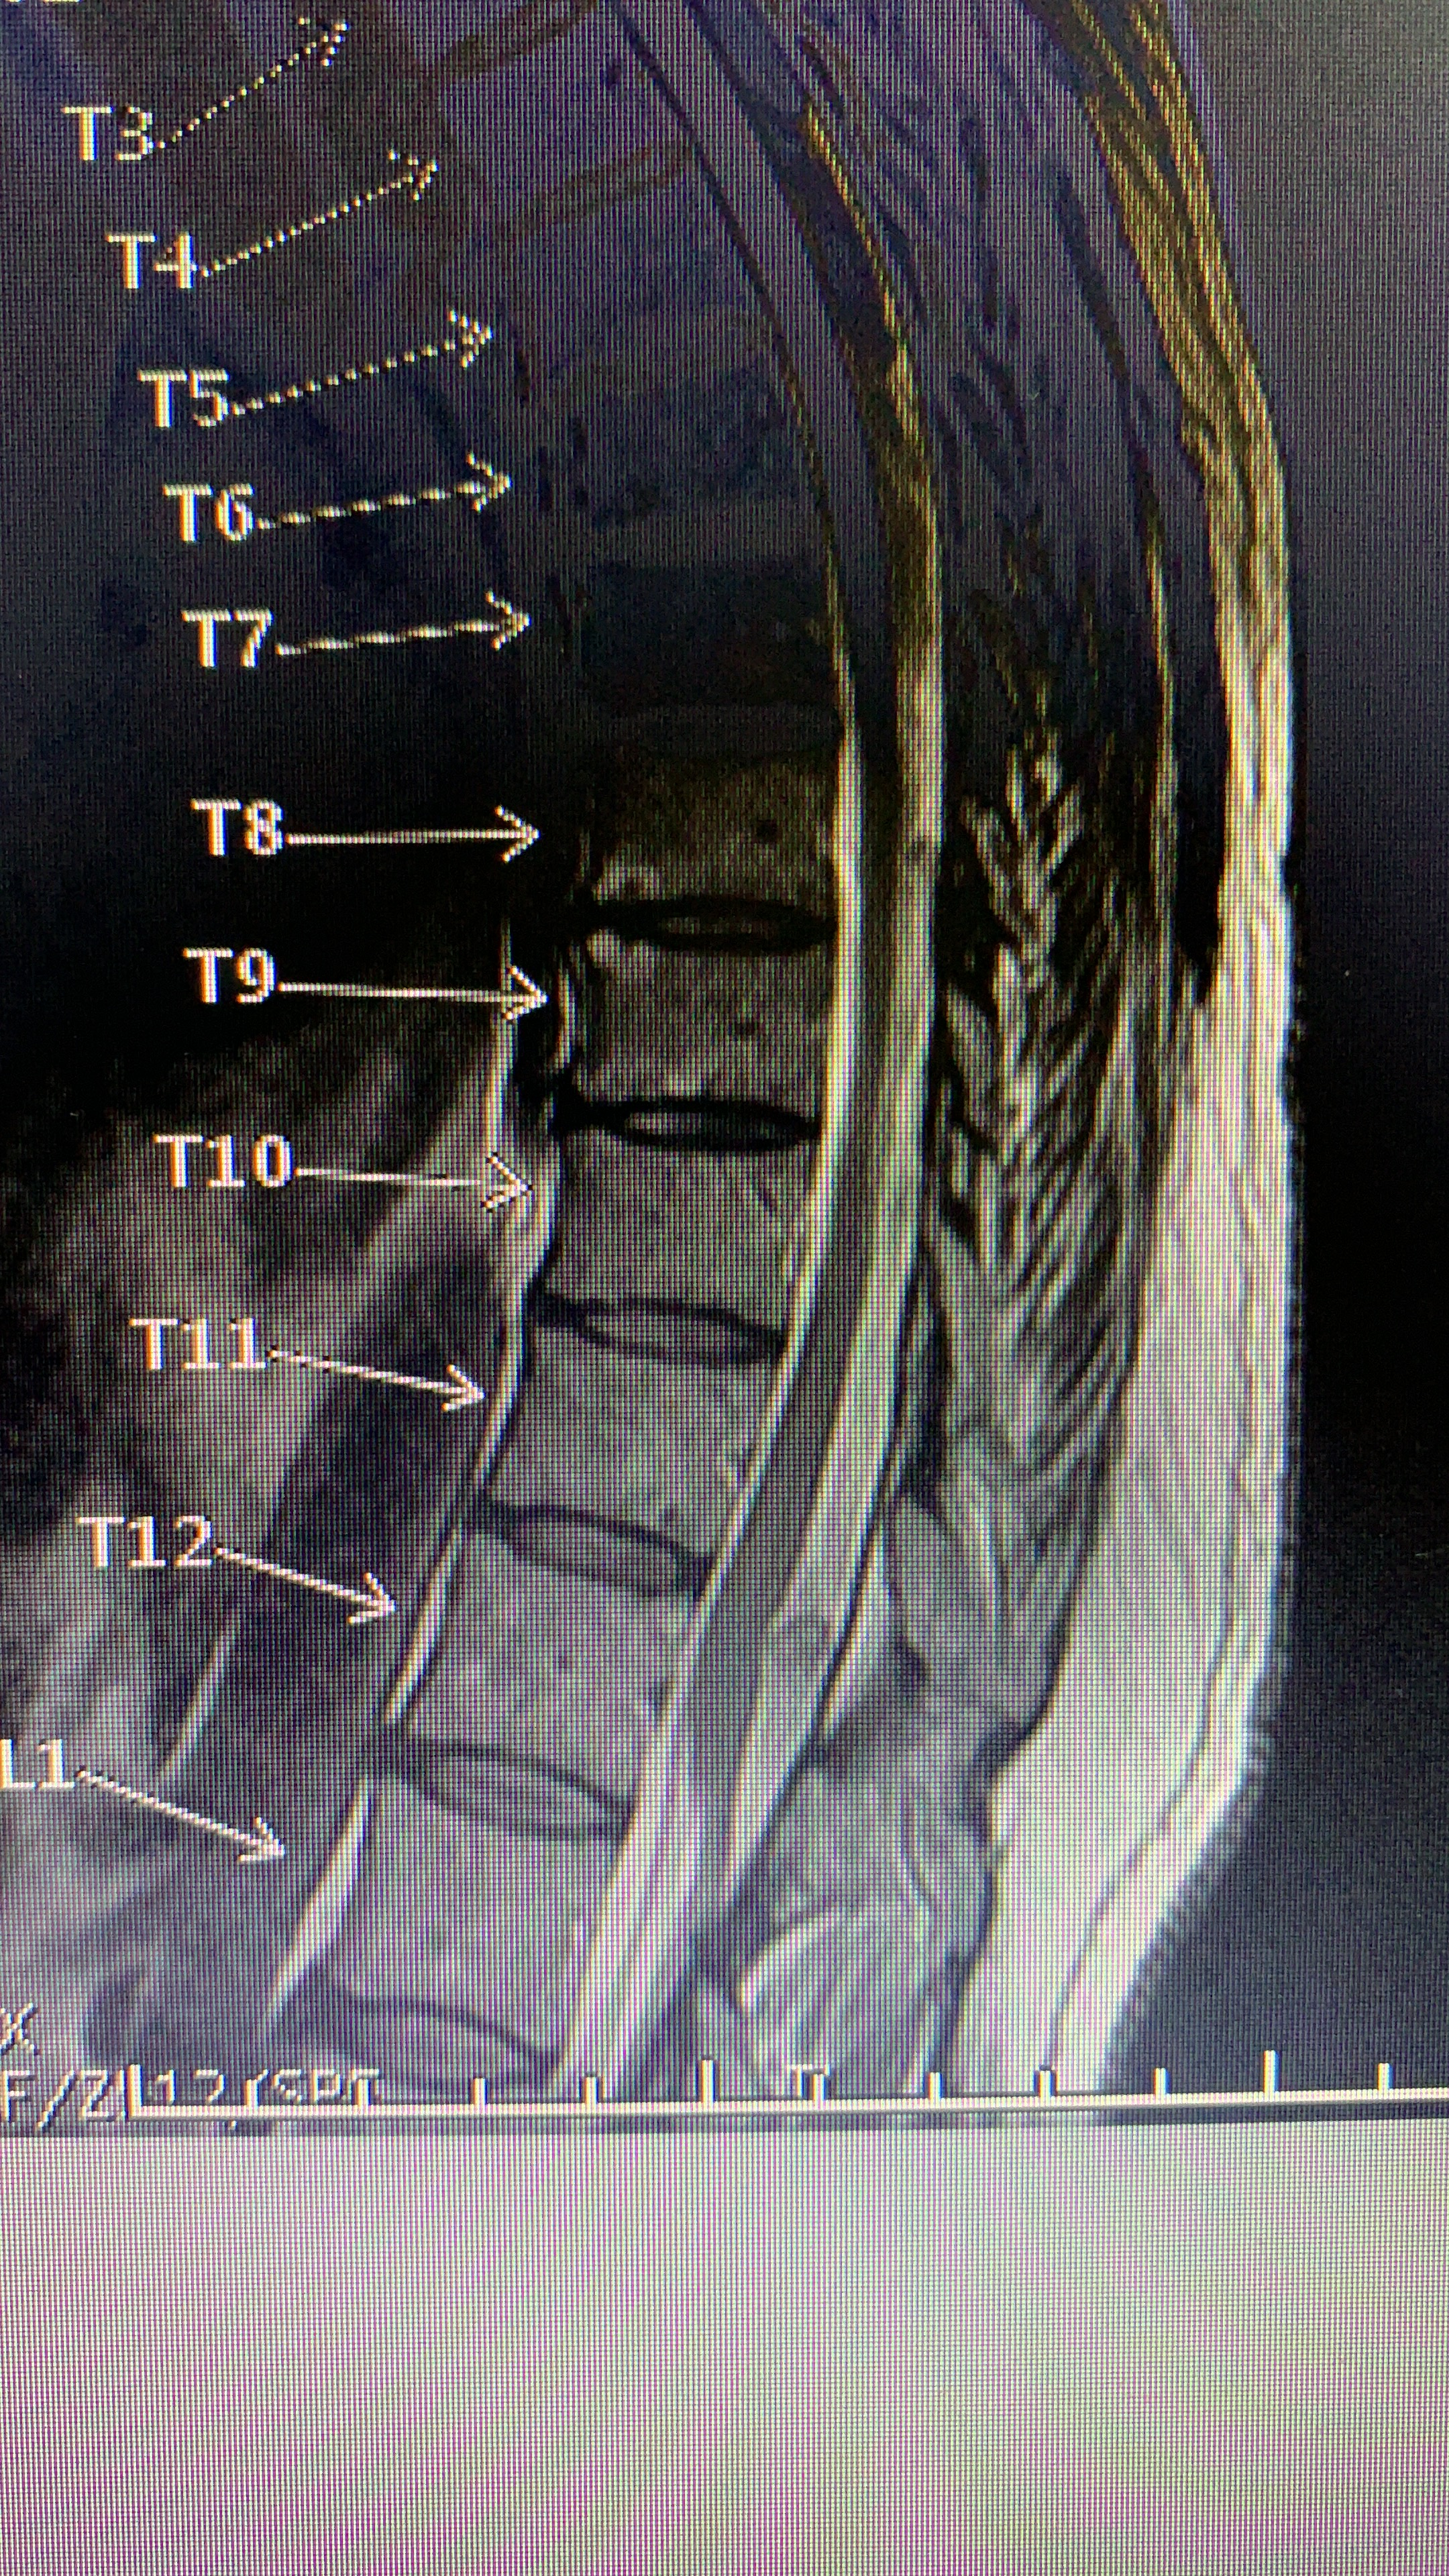

Galería de fotos clínica, servicios, cirugías, casos de pacientes Visítenos, ambiente limpio, agradable y seguro. Trabajando Operando en tiempos de coronavirus Dr Barquero Traumatologo Compartir en X (Se abre en una ventana nueva) X Comparte en Facebook (Se abre en una ventana nueva) Facebook Imprimir (Se abre en una ventana nueva) Imprimir Compartir en WhatsApp (Se abre en una ventana nueva) WhatsApp Enviar un enlace a un amigo por correo electrónico (Se abre en una ventana nueva) Correo electrónico Me gusta Cargando...